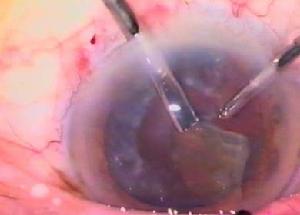

手術治療

晚期由於纖維組織增生,藥物及放射治療的效果都不明顯,眼球高度突出及視力出現嚴重障礙時,可以考慮手術治療,但應慎重選擇施行,因為手術後仍有復發可能。